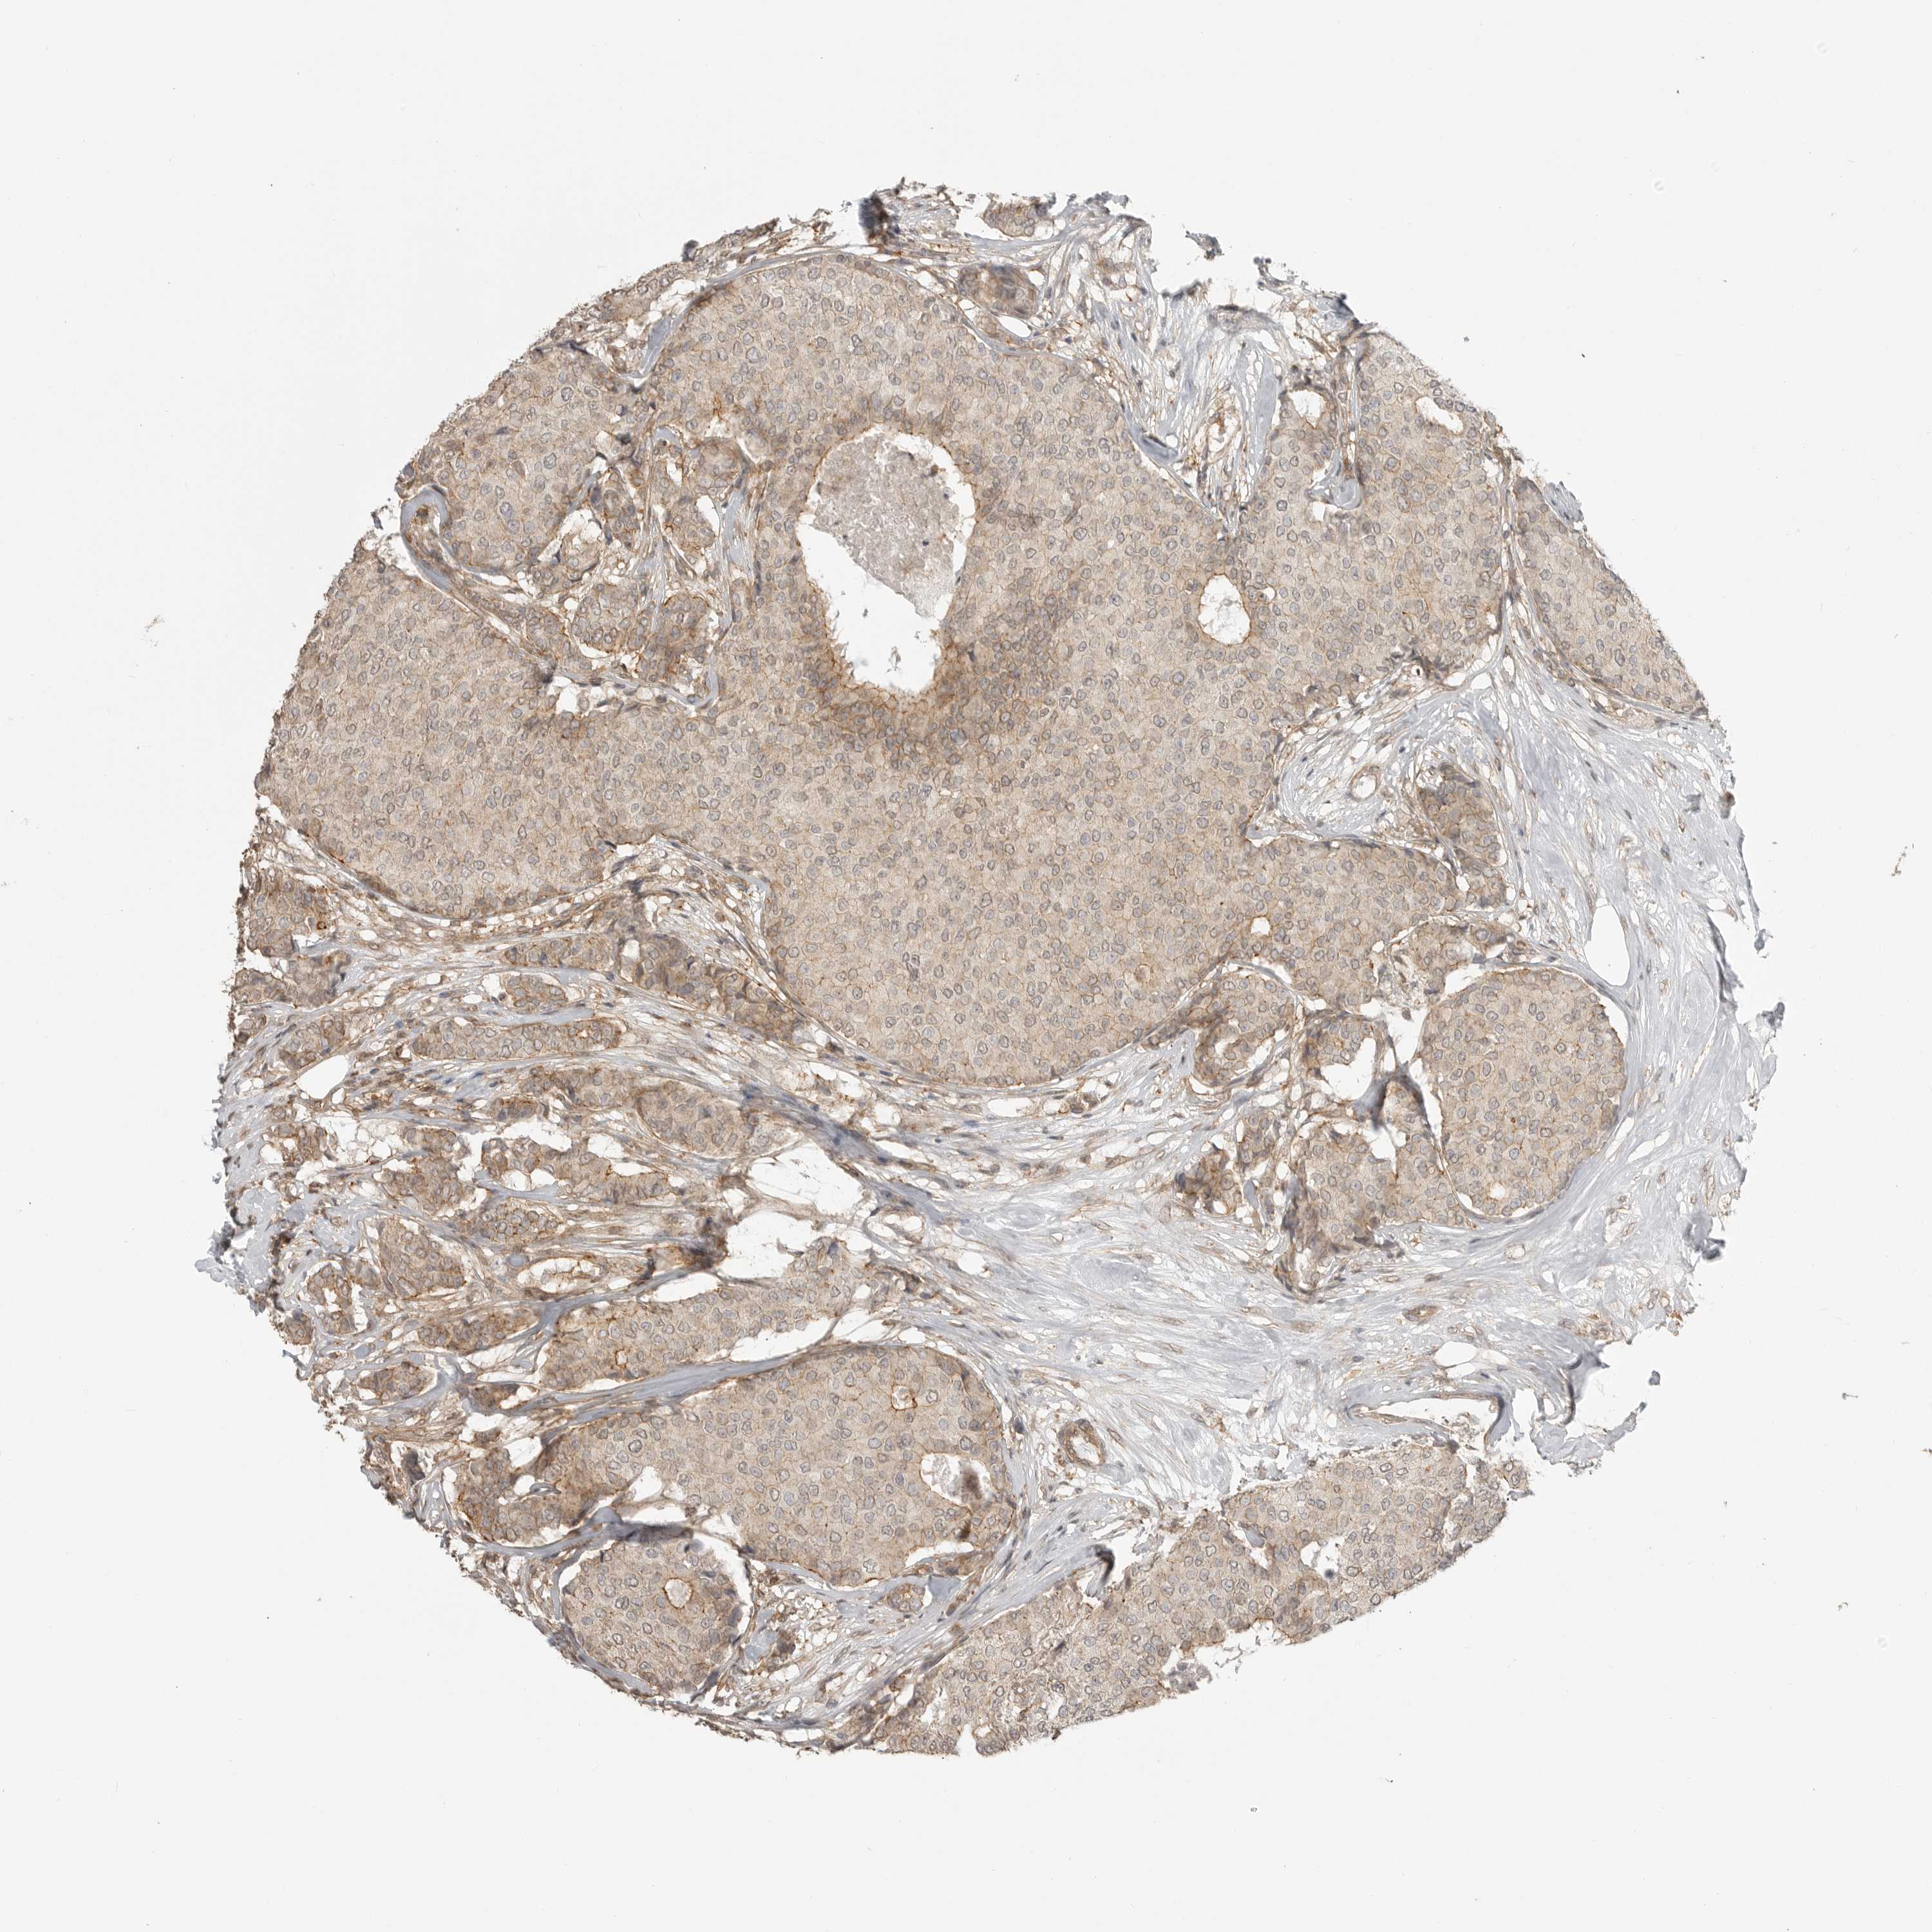

CANCER BREAST CANCER Show tissue menu

BRCA TCGA BRCA VALIDATION PROTEIN EXPRESSION